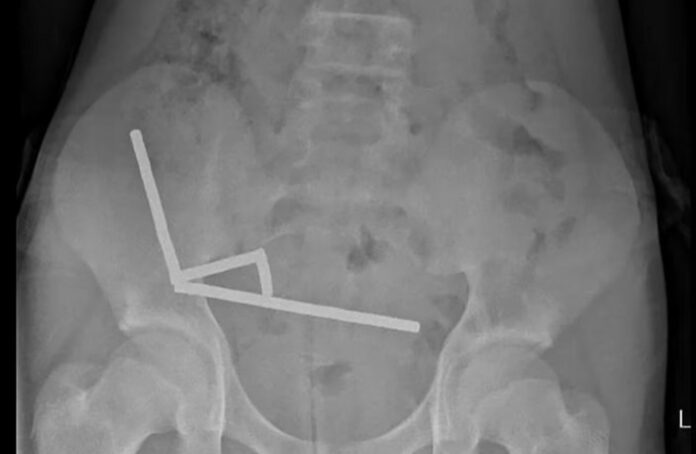

O adolescente suportou quatro dias de dor abdominal antes de buscar ajuda. No hospital, exames mostraram que os ímãs haviam se agrupado em quatro cadeias na região inferior direita do abdômen, unindo partes do intestino. Uma cirurgia exploratória revelou necrose por pressão em trechos do intestino delgado e grosso, exigindo a remoção parcial do órgão. Ele permaneceu internado por oito dias antes de receber alta.